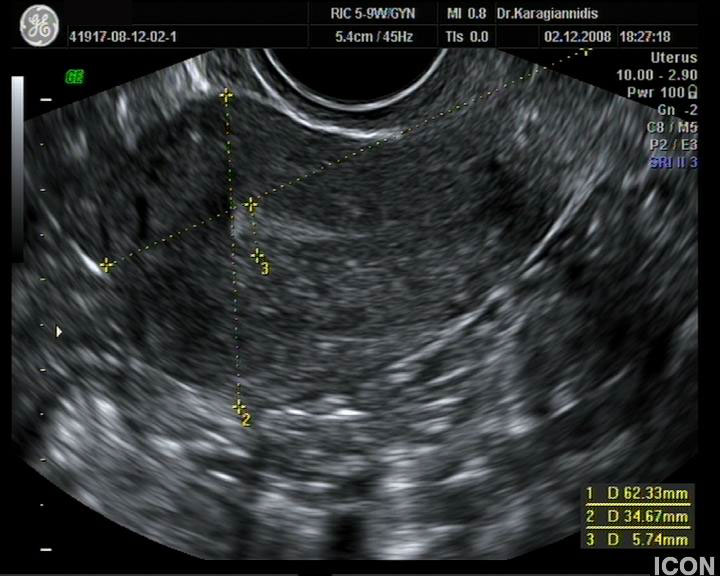

Ενδοκολπικός U/S έσω Γεννητικών Οργάνων